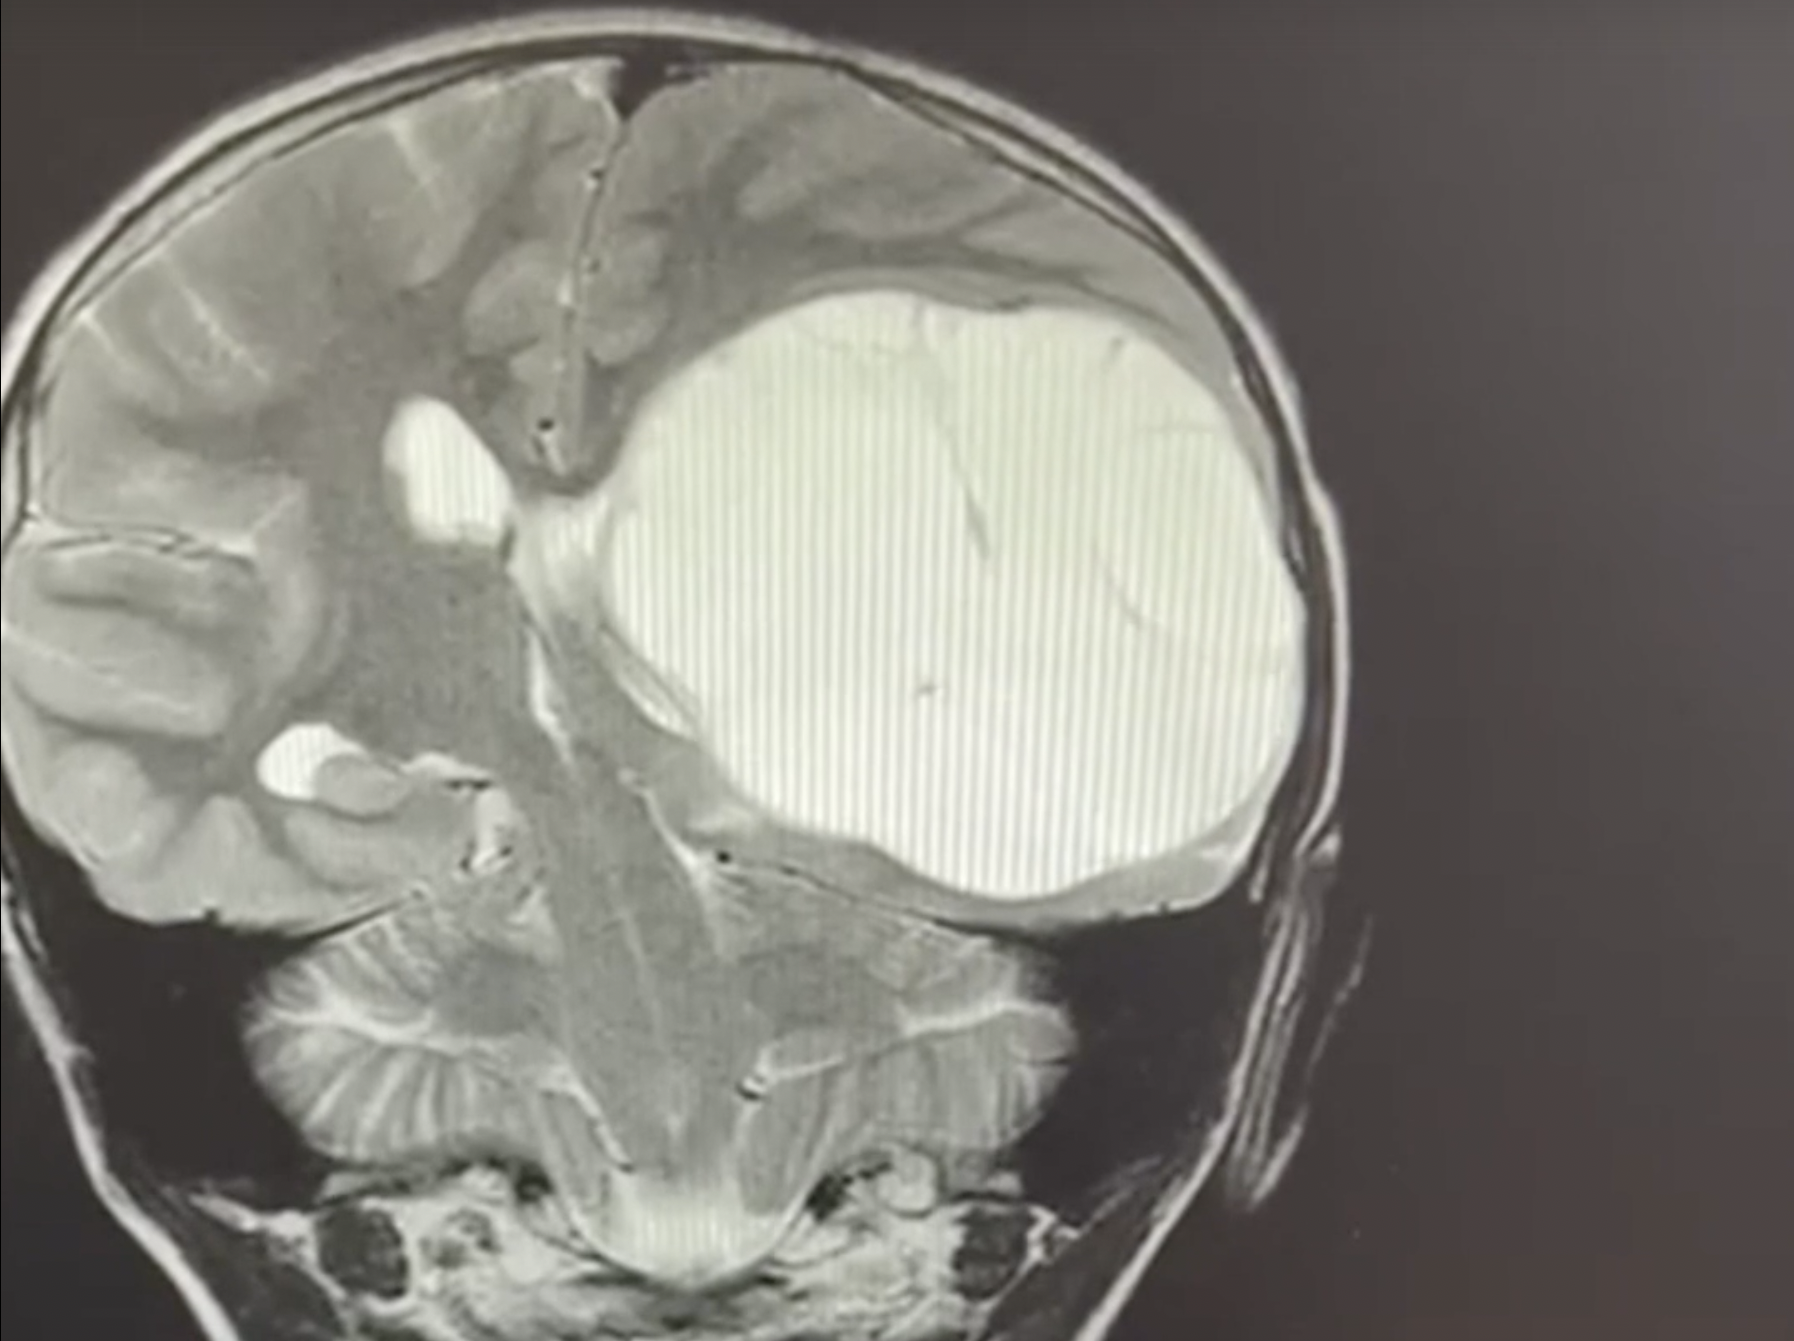

Киста В Голове Фото

Киста В Голове Фото 146 фотографий